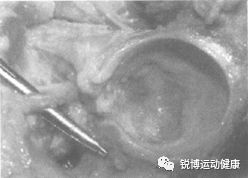

这时髋关节可能会过度伸展和过度外旋损伤,最常累及盂唇前缘,造成髋关节盂唇损伤;其他盂唇损伤见于髋关节畸形、不稳定、退变。

盂唇撕裂可能导致髋关节侧、髋关节前、腹股沟内侧甚至是臀部疼痛,取决于损伤的具体部位。前外侧盂唇损伤最常见。如果前盂唇受到应力,而且髋关节前推、旋转或踢腿时产生疼痛或不稳定感,应该怀疑是这种损伤。